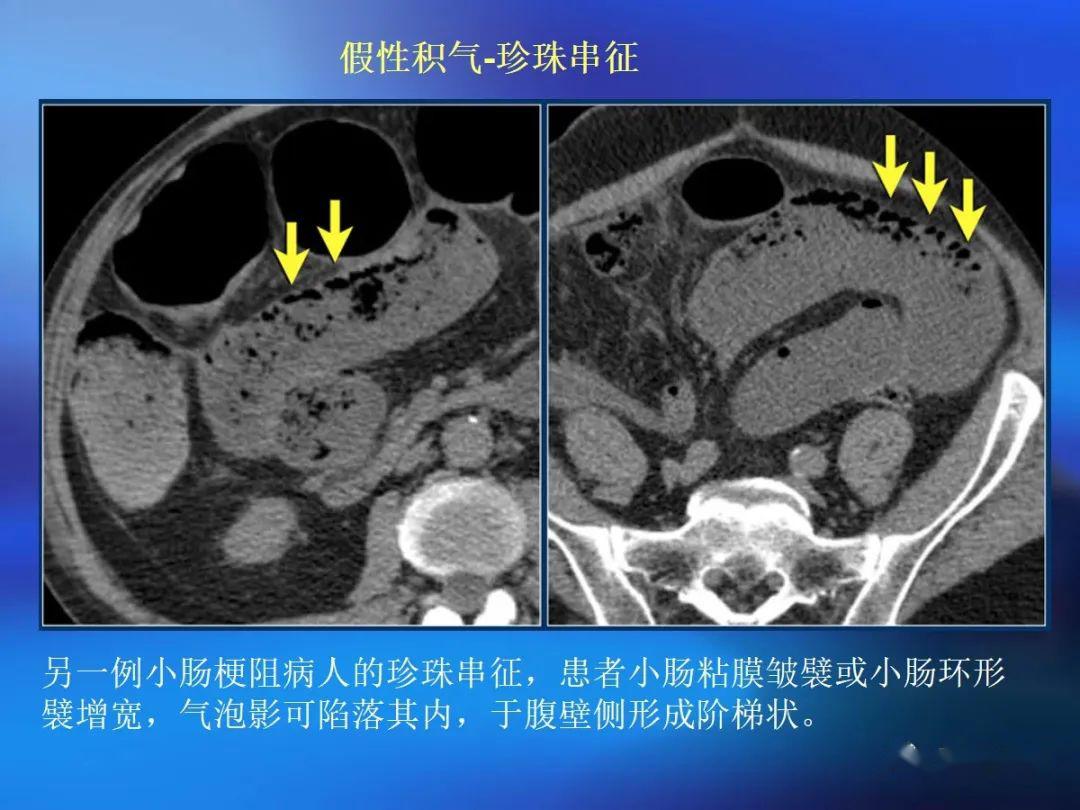

脂肪有时见于乳糜泻ct 评价肠壁增厚存在的问题肠道是蠕动的空腔器官